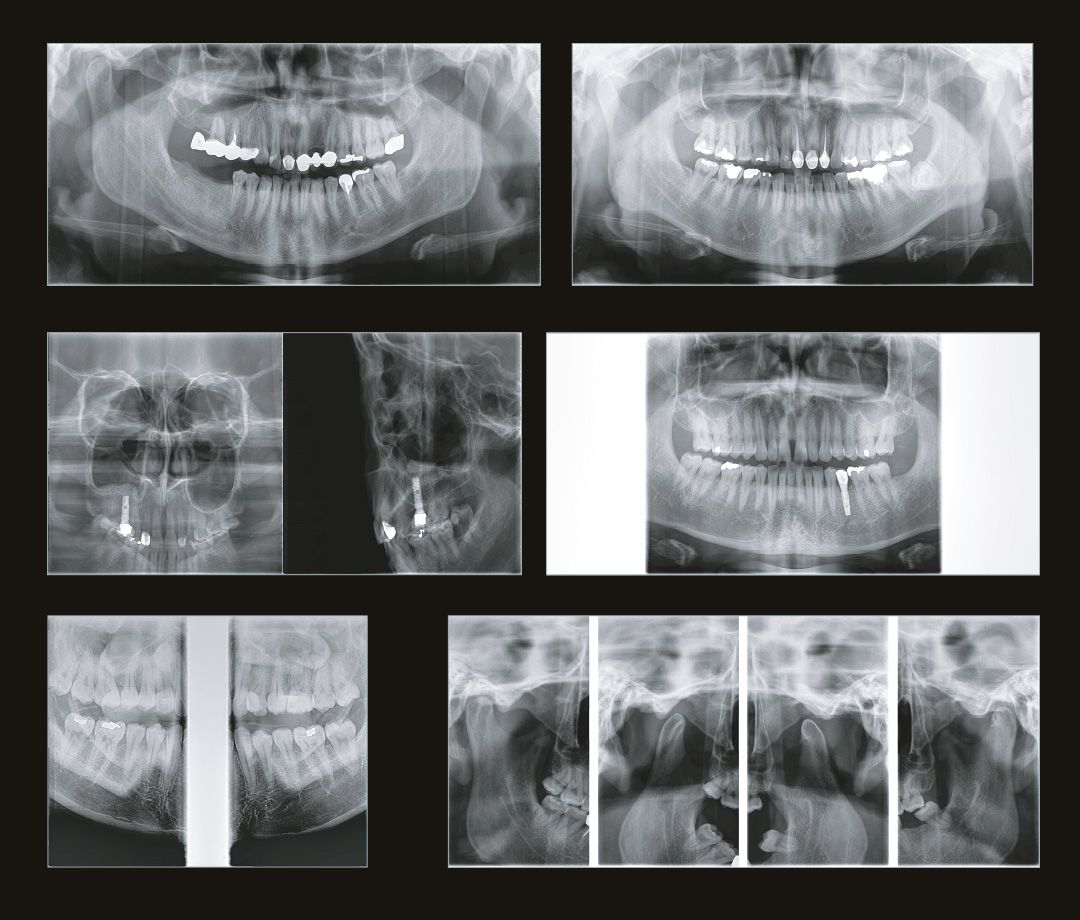

Современная стоматология уже давно не работает вслепую, и каждому из направлений стоматологии необходимо проводить рентгеновские исследования:

Стоматолог-терапевт по снимку видит не только кариес, а также способен оценить, как периодонтальные ткани, так и различные воспалительные процессы затрагивающие пульпарную камеру.

Стоматолог-хирург не способен производить свои манипуляции без снимка КТ, иначе он будет вынужден действовать вслепую, не сумев оценить анатомию области вмешательства.

Стоматолог-ортопед не сможет гарантировать надежность конструкции без правильной оценки стабильности опорных зубов при помощи снимка КТ.

Стоматологу-ортодонту, чтобы правильно простроить план лечения, помимо слепков, так же нужен снимок КТ.